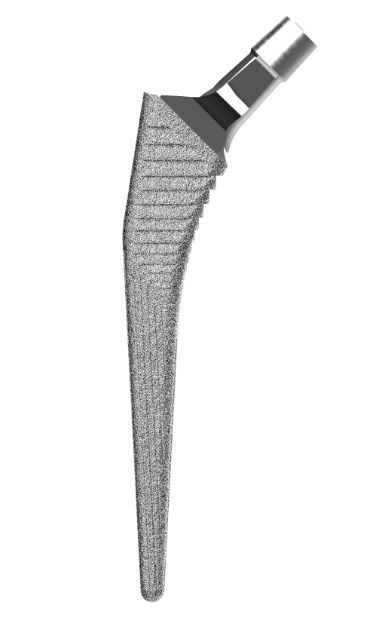

–С–µ–і—А–µ–љ–љ—Л–µ –љ–Њ–ґ–Ї–Є